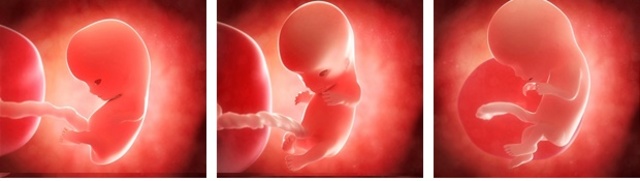

• segundo mes

segundo mes

El cuerpo llega a medir cerca de 3 cm. los rasgos de la cara se empiezan a definir asi como sus extremidades

• primer trimestre

primer trimestre

El feto mide 9cm. y pesa entre 15 y 20 gramos. La cabeza disminuye su ritmo de crecimiento, para estar más proporcionada respecto al cuerpo. Va tomando forma de humano